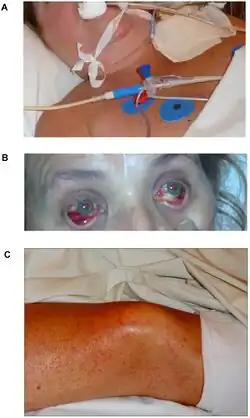

Only 5 cases of this virus have ever been reported; all 5 were identified in September and October 2008, and 4 were fatal. Those infections that proved fatal caused death within 10–13 days of showing symptoms. All four patients in which infection proved fatal first showed signs of improvement and then went into respiratory distress, displayed neurological problems, and had circulatory issues that resulted in collapse.[2] The discovery of this novel virus was described following a highly fatal nosocomial (hospital) outbreak of VHF in Johannesburg.[11][12] The identification of this virus was the first new arenavirus discovered in over 40 years.[13]

Symptoms and signs

VHF symptoms appear similar to other viruses of the same family, such as Lassa fever. The known symptoms include:[8]

- Swelling in neck/face

- Sore throat

- Diarrhea

- Rash

Blood tests of those infected revealed elevated liver values, white blood cell counts that were first low and then elevated over time, and low platelet counts.[8]In terms of the diagnosis of Lujo hemorrhagic fever the following is done:[15][16]

Treatment

In-depth research into Lujo virus and its treatment have been difficult because of the lack of economic and cultural stability of the regions where the only known cases have occurred. Under Treatment with oral ribavirin treatment, the patient 5 continued to deteriorate but the treatment shifted to i.v on day 8 it seemed to have cured the only surviving patient with Lujo Virus, but because the 5 affected in 2008 have been the only cases identified, there has not been much opportunity for further research.[16][12]